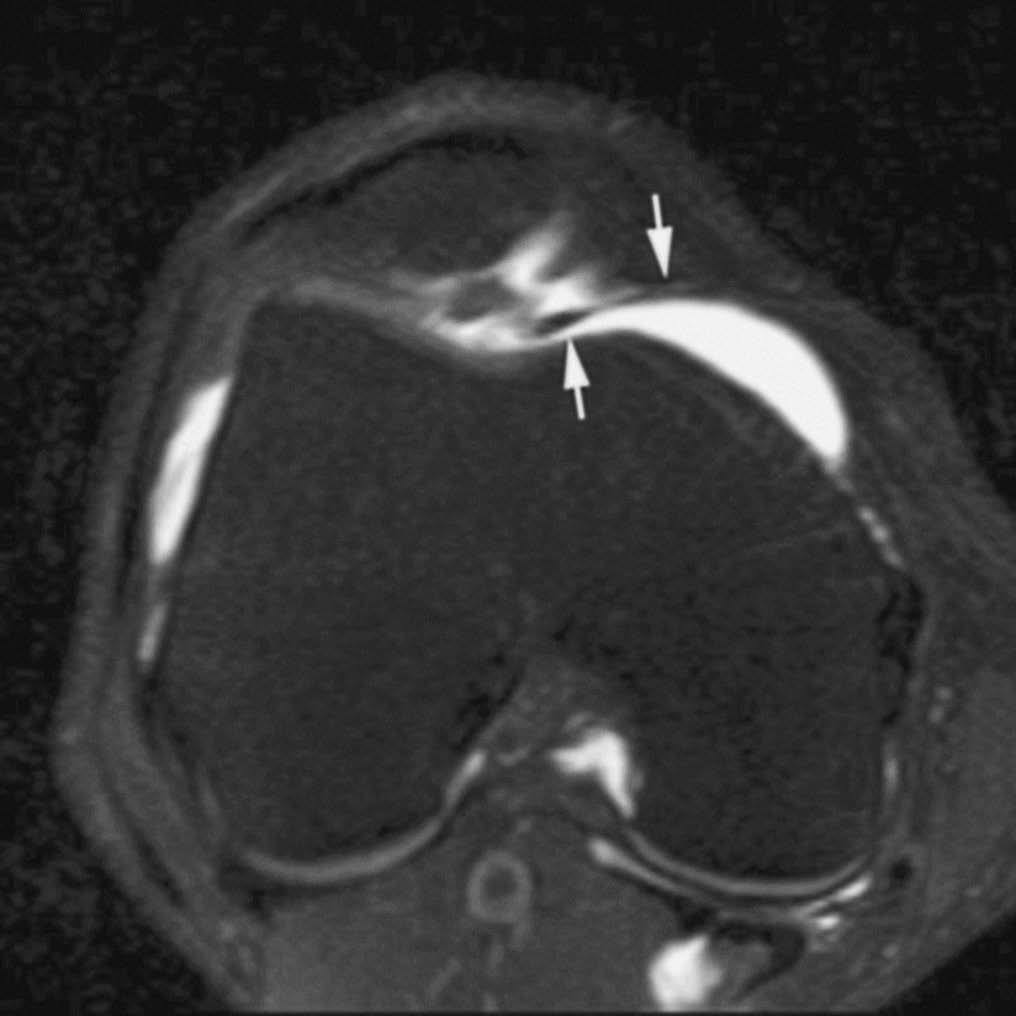

La RMA es una técnica con mayor eficacia diagnóstica en la valoración de las roturas meniscales recurrentes. Después de meniscectomías parciales, la capacidad de diagnosticar roturas recurrentes depende de la cantidad de menisco extirpado. Cuando la resección meniscal es menor del 25% los criterios de rotura en RM son los mismos que en la rodilla no operada --la fiabilidad de la RMA es similar a la de la RM en estos casos--. Cuando la resección es mayor del 75% la clínica del paciente no se asocia a las rerroturas meniscales. En los casos de resección entre el 25 y el 75% los criterios de rerrotura se basan en la introducción de contraste en el remanente meniscal (fig. 6)1,15,16.

Fig. 6.--Rerrotura de asta posterior del menisco interno. A, B) Corte coronal potenciado en T1 y corte sagital de RMA potenciado en T1 con técnica de supresión grasa en los que se observa introducción del contraste en el defecto meniscal.